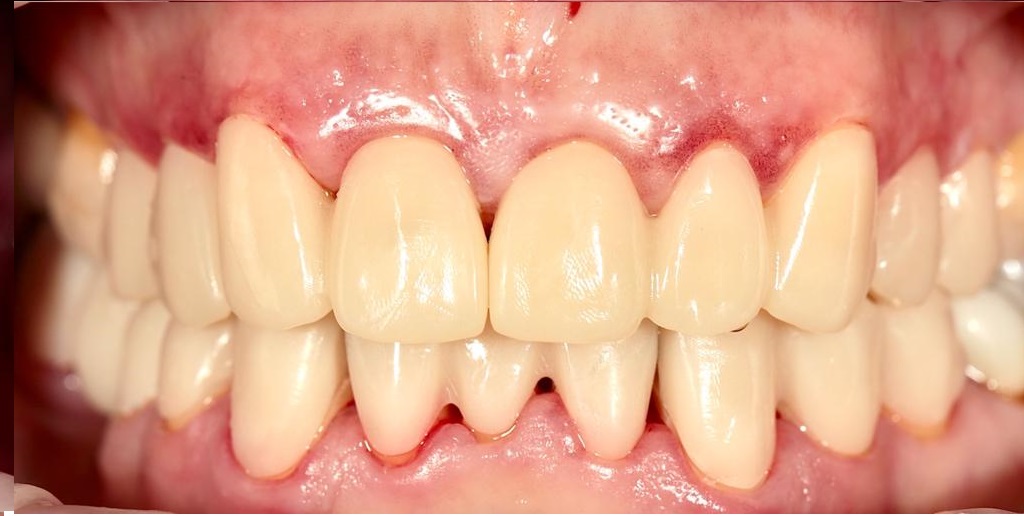

Имплантация зубов

Установлено 4 имплантанта Osstem во фронтальном участке верхней челюсти.

Протезирование выполнено коронками из оксида циркония с фиксацией на абатменты из оксида циркония.